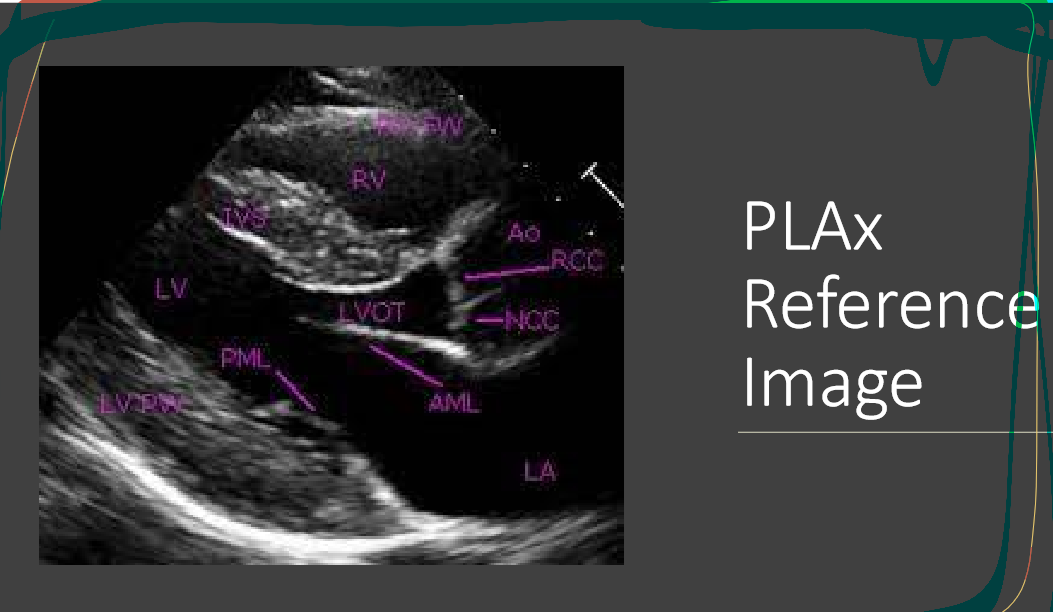

what are the white labels

RV

LA

LV

LVOT

AO

What is this view

parasternal long axis of the heart